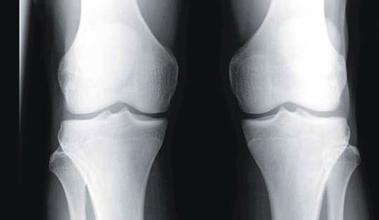

骨刺到底是不是病,治疗骨刺的偏方